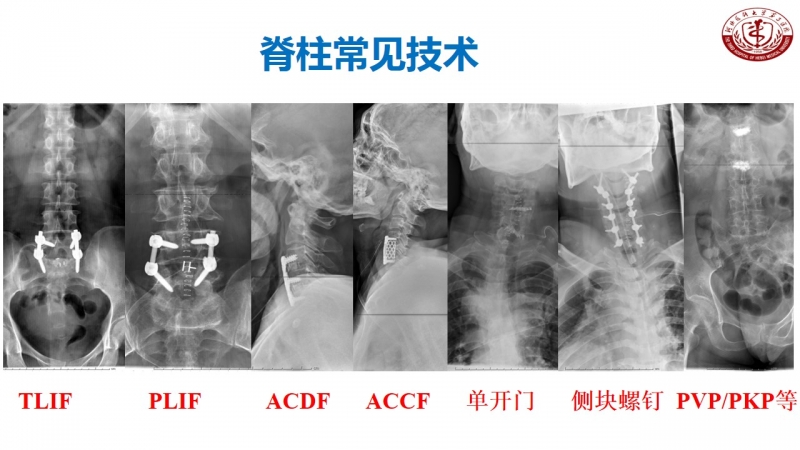

作为脊柱外科的主任,丁文元教授时刻不忘科室的建设和发展。目前,河北医科大学第三医院脊柱外科共有33人,其中主任医师9人,副主任医师4人,主治医师11人,分三个病区,共120张床位,年门诊量66000余人次,年手术量4500余台,并开展了一系列脊柱高难手术,如复杂脊柱畸形截骨矫形术、复杂严重颈椎病前后路手术、胸腰椎前后路手术、上颈椎腰骶部复杂手术以及脊柱各种微创手术。

脊柱外科目前所开展的诊疗技术(滑动查看)